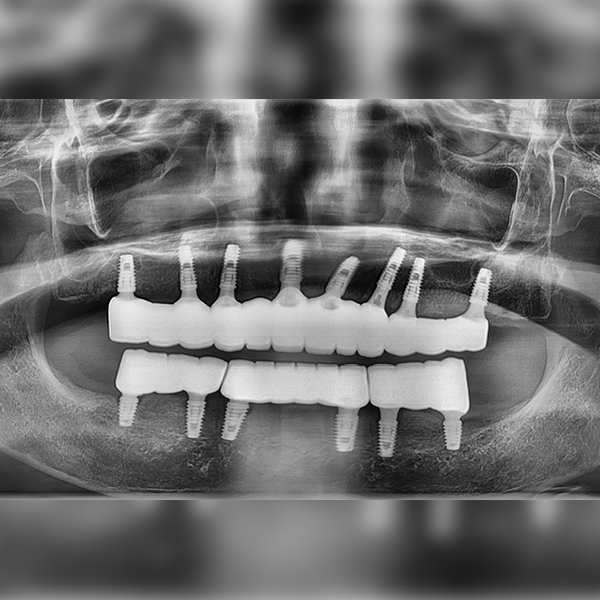

Nha khoa One Day

Toàn hàm/Toàn bộ / Ghép xương | Tiền mê

Trường hợp 53 Ông/Bà Im*ja, 70 tuổi 2021-03-30 / 2021-04-02

After After

Before Before

Drag to compare